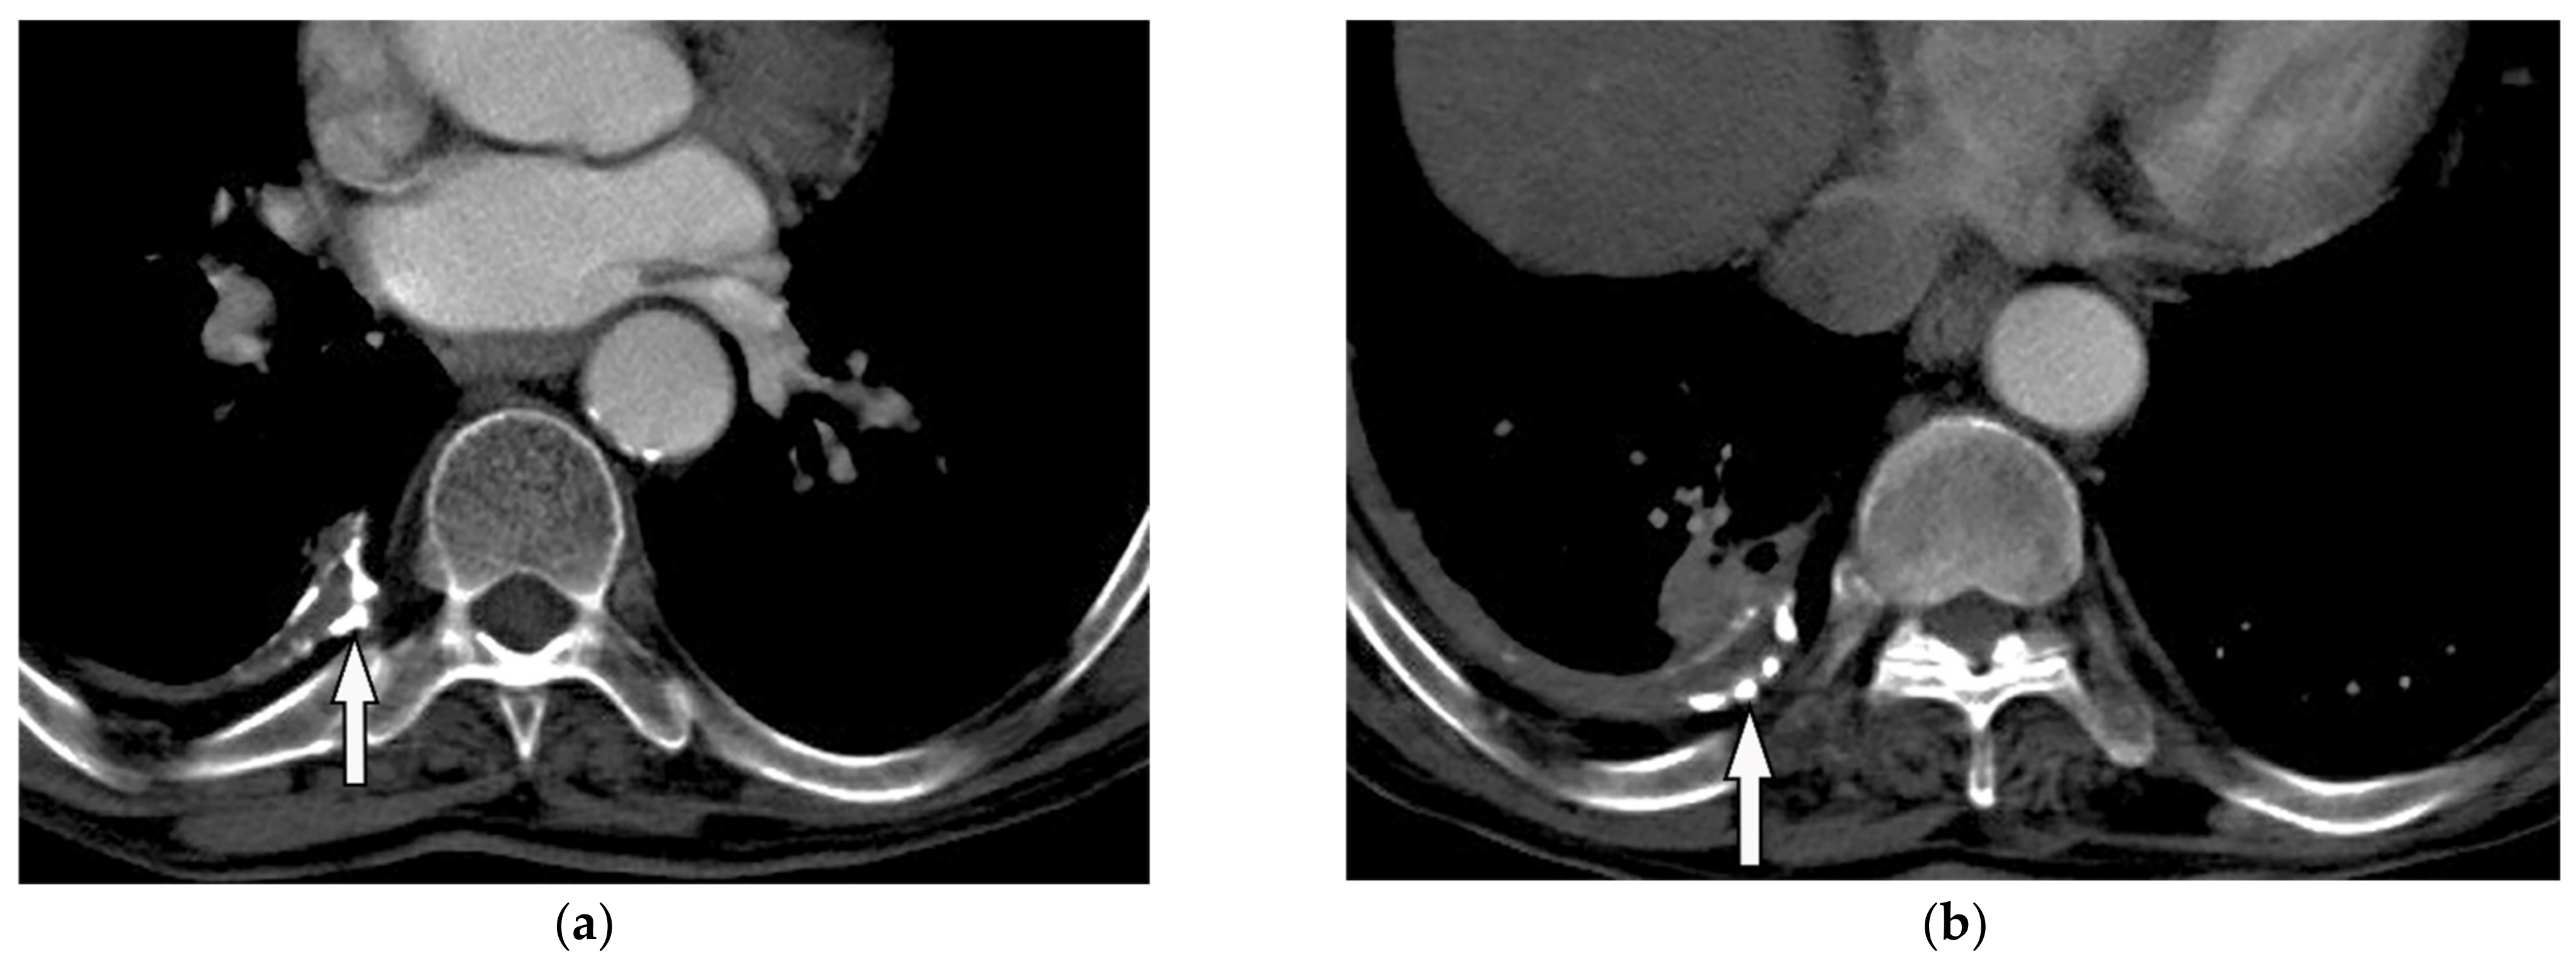

| Schwannoma | Well-defined mass with homogenous attenuation, “fat-split” sign, internal calcification in long-standing schwannomas, postcontrast enhancement except for areas of necrosis. | T1W: iso or slightly hyperintense; T2W: significantly hyperintense |

| Neurofibroma | Well-circumscribed mass with smooth margin and soft tissue attenuation, possible internal calcifications, rib erosion, neural foramina widening because of tumor extension along with the spinal nerve roots. | T2W, T1WFS + C: so-called “target sign” appearance: hyperintense rim and hypointense center |